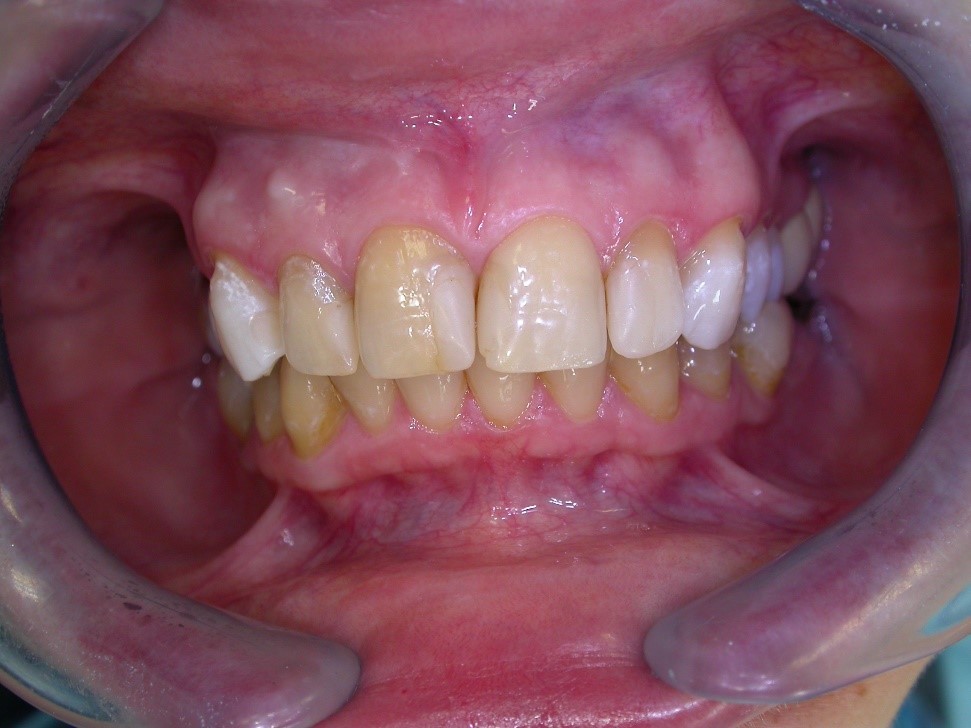

Úprava estetiky chrupu pomocí keramických fazet

Keramické fazety jsou vhodným řešením pro estetickou úpravu přední části chrupu ať již z důvodu tvaru zubů, jejich poškození či trvalého nežádoucího zabarvení. Vyžadují menší preparaci vlastního zubu, jsou také zhotovovány v zubní laboratoři, a proto je potřeba dvou návštěv v ordinaci.

Ukázky naší práce